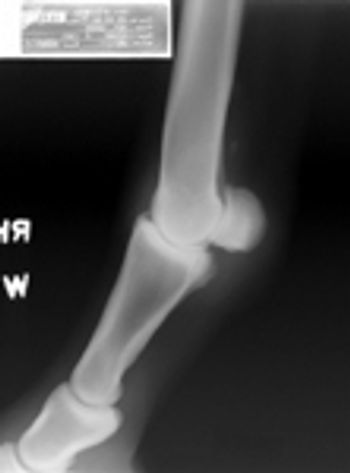

An 11-year-old 54.9-lb (27-kg) neutered male mixed-breed dog was presented to Long Island Veterinary Specialists for evaluation of lethargy and depression of several days' duration.